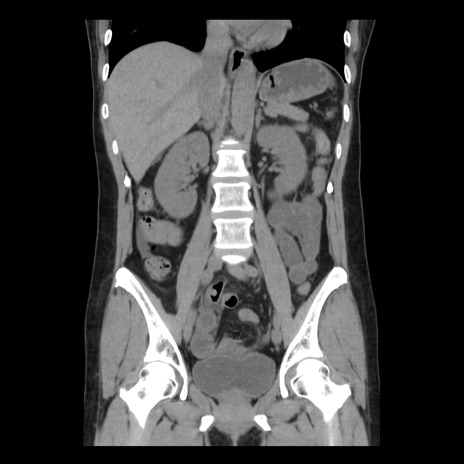

症例10(冠状断像)

【症例】 50歳代女性

【主訴】 腹痛

【現病歴】前日生レバーを食べた。今朝に排便あり。 昼前に突然発症の腹痛を生じ、当院救急外来を受診した。

【既往歴】 子宮筋腫にてで子宮全摘後

【身体所見】 意識清明、腹部:平坦、軟、下腹部やや左を中心に圧痛・反跳痛あり、筋性防御あり

【データ】WBC 7800、CRP 0.07